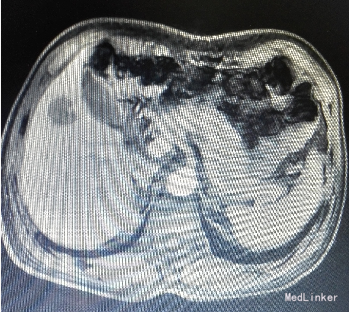

主诉:反复右上腹痛1年余,发现肝占位1周。 病史:患者1年前无明显诱因出现右上腹隐痛,持续性,疼痛无他处放射,无诉其他不适。到当地医院就诊,上腹部彩超未见异常,未行特殊处理。1年来患者症状反复,平均1~2天一次,程度、性质大致同前。1周前至当地市医院检查,上腹部彩超与CT均提示“肝右叶占位性病变”,大小约2.5*2.5cm,考虑肝癌可能性大。现为行进一步治疗入院。

入院后行腹部CT检查,提示肝S5病灶,考虑小肝癌可能性大。